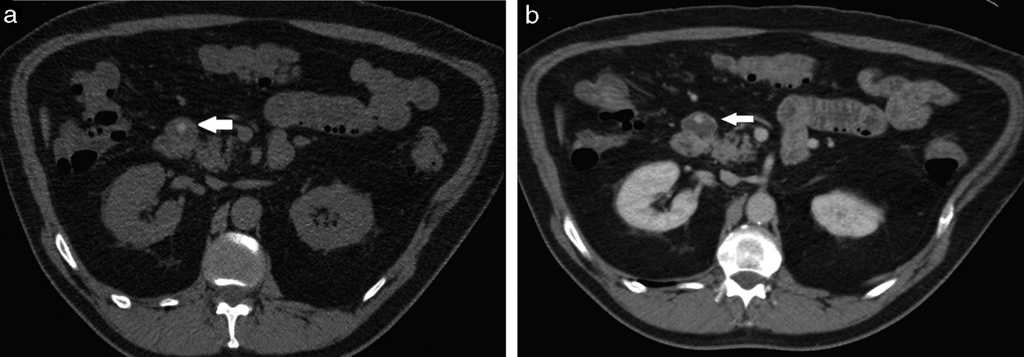

Diverticulitis y perforación (5%): se visualiza engrosamiento parietal y deformación de los contornos del divertículo complicado, con aumento de la densidad de los planos grasos adyacentes y formaciones ganglionares reactivas asociadas, generalmente en rango no adenomegálico. La TCMD descarta o confirma la existencia de colecciones abscedadas o de neumoperitoneo2 (figs. 2–5).